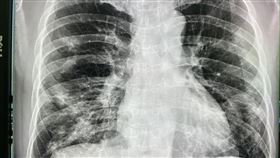

獨/肺部「白了一片」 這癌症好發年輕人

沒抽菸胸痛就醫 男大生淚崩:肺只剩一邊

一名21歲男大生無不良習慣、也不抽菸,平時喜歡戶外運...